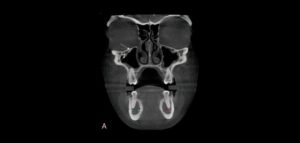

Se sabe que la tomografía computarizada de haz cónico (CBCT) produce exploraciones tridimensionales de la dentición, las estructuras duras maxilofaciales y la relación de las